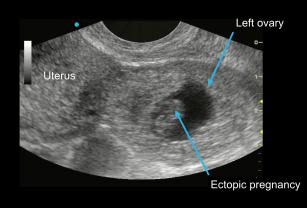

Evaluating for an ectopic pregnancy using point-of-care ultrasound (POCUS) 8th Mar 2017 - Viveta Lobo, MD After reviewing this lesson, you will know how to evaluate for an ectopic pregnancy using Point of Care ...